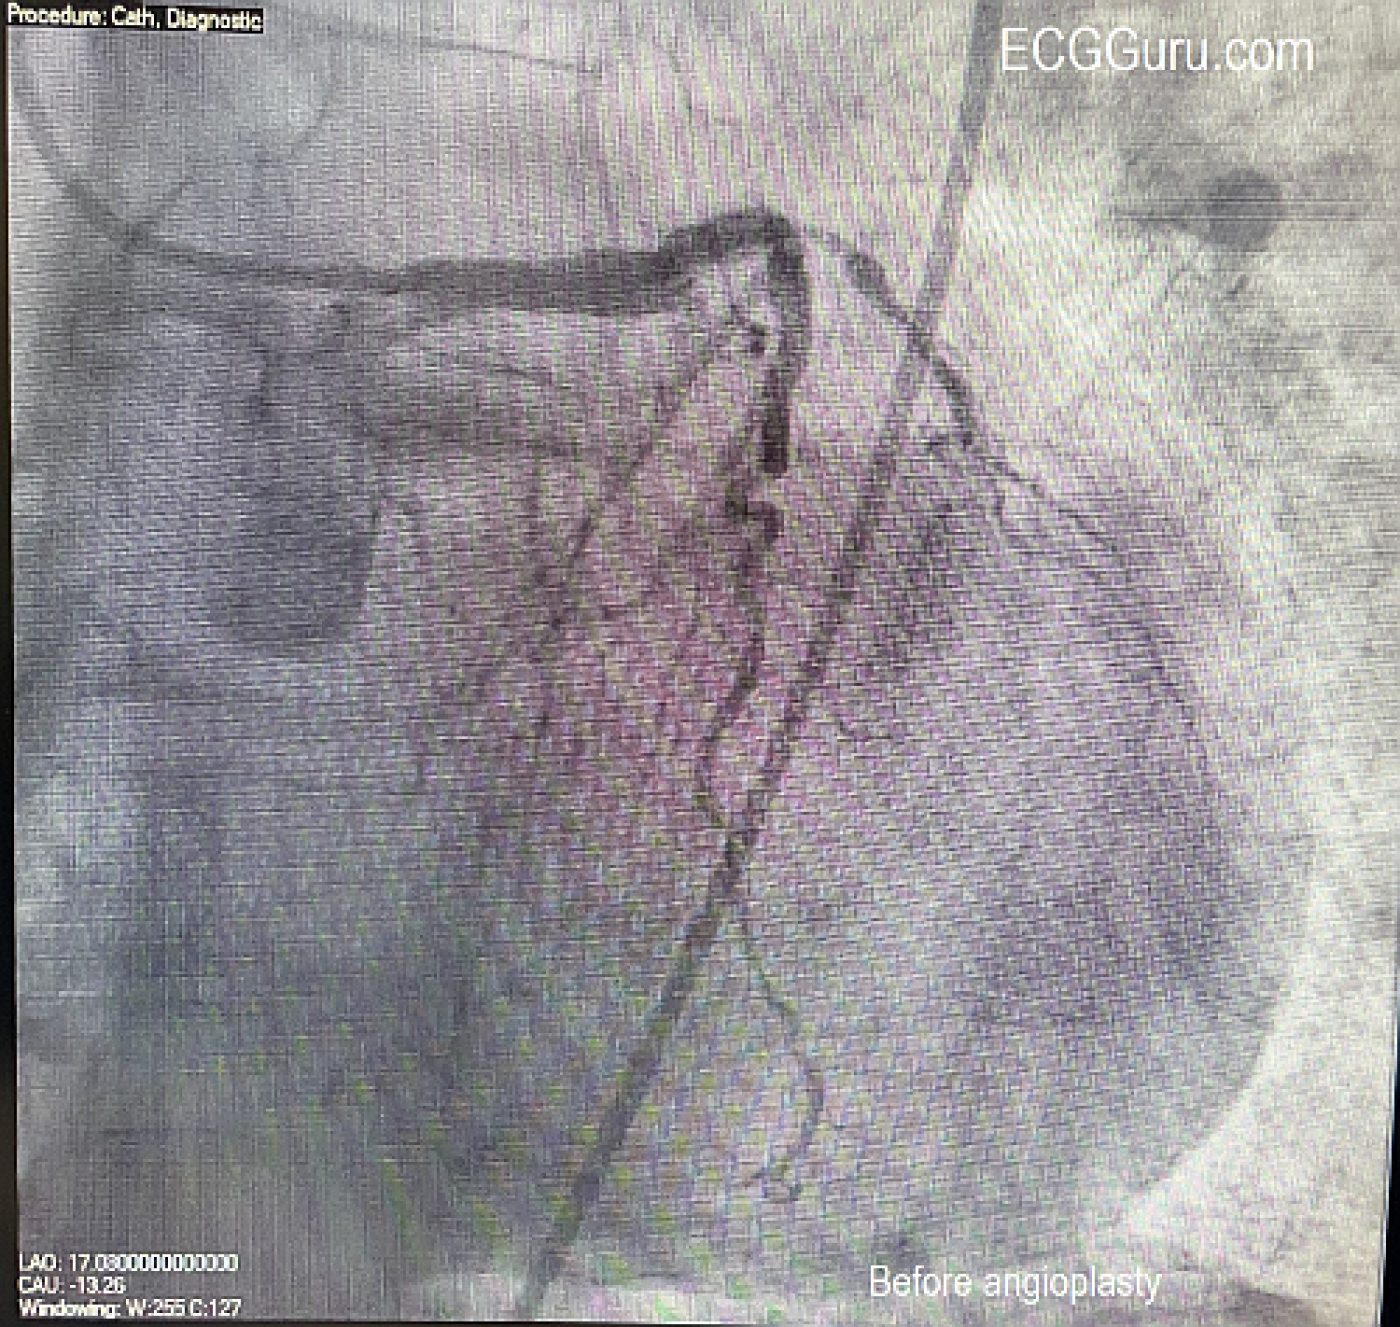

The Cath Lab: In the cath lab, the circumflex artery was found to be totally occluded. When a wire was introduced, circulation opened up, revealing an extensive collateral system from the circumflex to the area usually supplied by the RCA (inferior/posterior wall). The right coronary artery (RCA) was found to have chronic total occlusion (CTO), confirmed by the presence of a collateral system from the circumflex. The arteries show extensive disease. The patient was stabilized with an Impella (mini ventricular pump) placed due to cardiogenic shock. The ECG shows how extensive the damage can be when coronary circulation is relying on one coronary artery system (LCA) to supply the entire heart, and that a large part of that supply (circ) is acutely occluded.